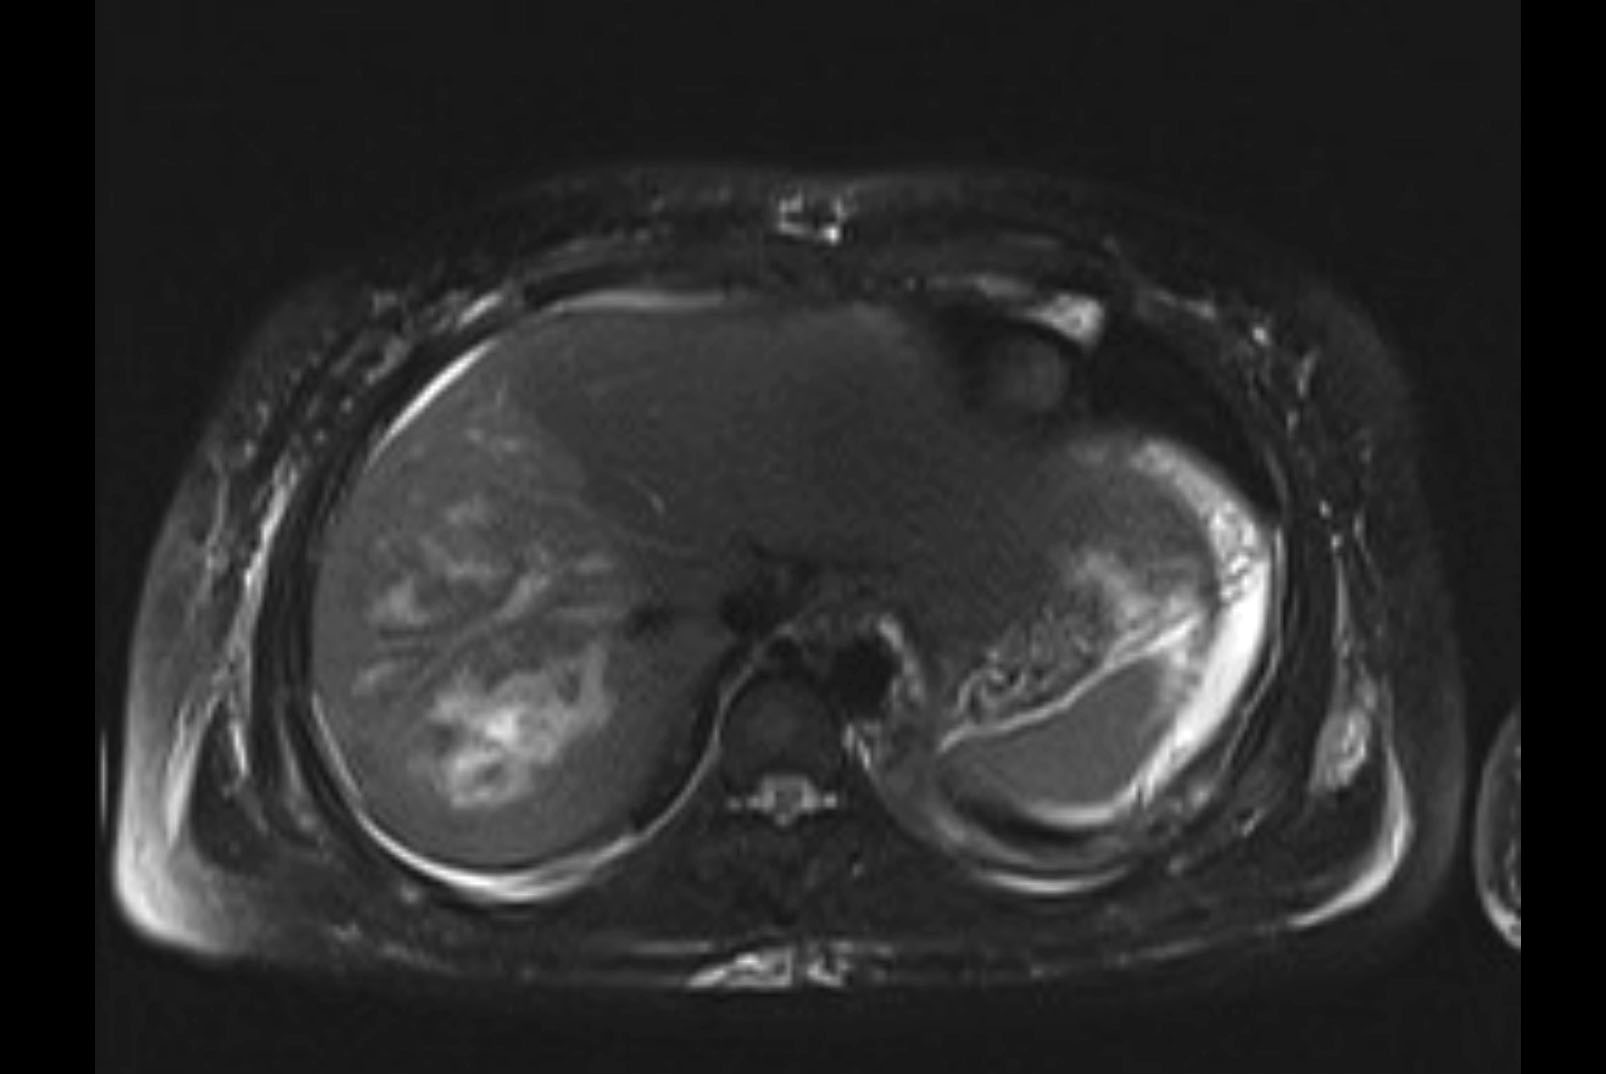

Imaging Analysis

Look through the patient's CT scan to identify any areas of concern for the necessary procedure.

MRI T2

Based on initial findings, which issue(s) would you be most concerned about?